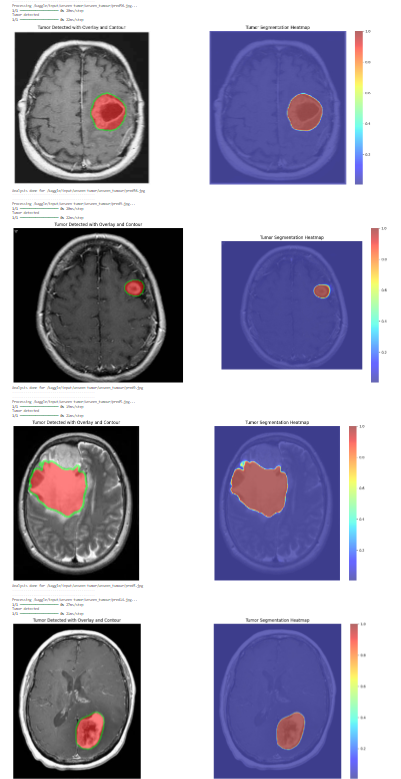

2. U-Net for Segmentation: A custom-built U-Net architecture pinpoints the exact tumor location, providing a visual overlay for clarity. The model employs Dice loss for enhanced accuracy in pixel-level predictions.

The system produces intuitive and visually enriched results:

The solution is scalable, handling batch MRI scans from a directory. Each scan is processed, classified, segmented, and annotated with heatmaps, making it an invaluable tool for clinical applications requiring high throughput.